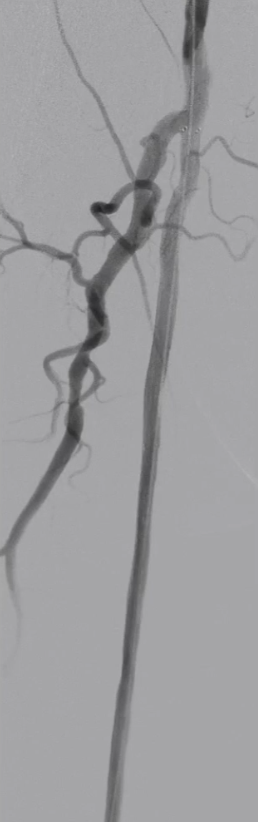

手术结果:

血流通畅,解剖与功能双重改善

最终造影显示:支架定位准确、形态良好,股浅动脉、腘动脉及膝下动脉显影清晰,血流通畅。

体格检查:右侧胫后动脉恢复正常搏动;

ABI:右侧从术前0.65提升至0.92,缺血症状显著改善。

CTA复查:支架内血流通畅,无明显内膜增生,证实手术远期有效性。